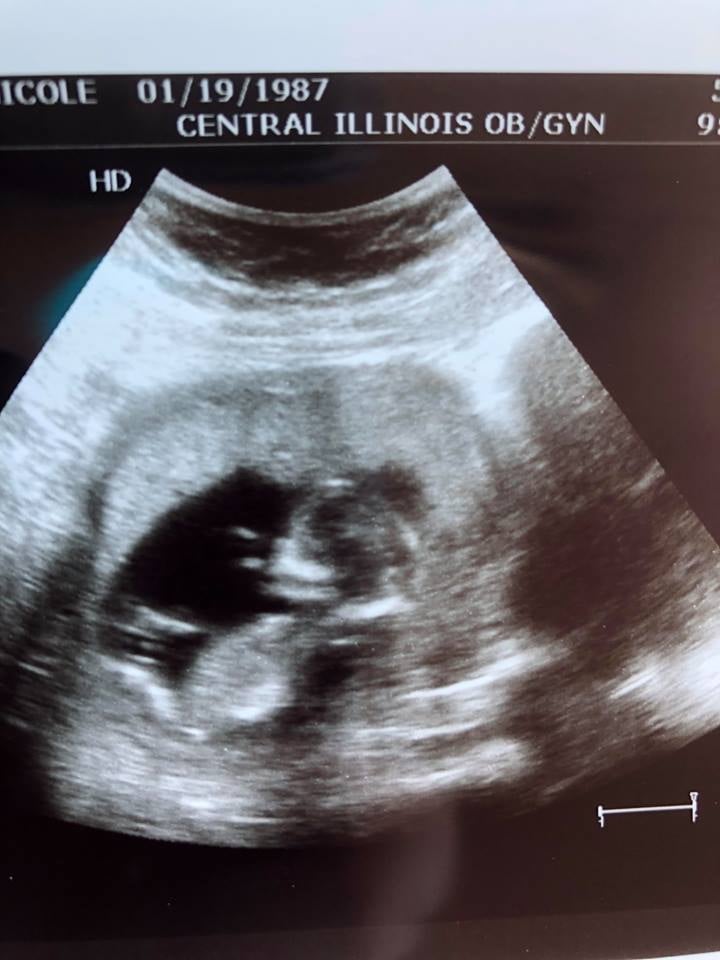

We had our first ultrasound at 10 weeks (I am 12 weeks now - due date at 11/19/18 - which is 3 days before my husband’s bday lol) I am a FTM, and thought this was so incredible. Seeing everything clearly definitely settled my nerves - the baby’s heart was fluttering at 154BPM and moving around like crazy! Our ultrasound tech showed us that she thinks it’s already a boy (my husband was THRILLED lol!) but we are waiting until W20 to confirm and before we start purchasing for the nursery. Now we can finally announce!